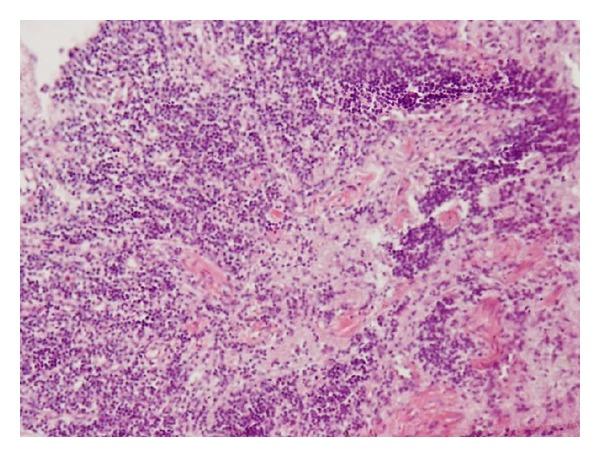

Dengue is endemic in Sri Lanka and the physician should be aware of different and unusual presentation of the illness. Rhabdomyolysis is a well-known complication following many viral and bacterial infections; however, only a few cases have been reported with dengue viral infections. Further occurrence of coinfection by dengue and bacteria such as methicillin-resistant Staphylococcus aureus (MRSA) has been underestimated, and few reports have been published so far. This case describes a 17-year-old boy who presented with prolonged severe myalgia, dark red urine, and a febrile illness that was diagnosed as having dengue viral myositis, dark red urine, and a febrile illness that was diagnosed as having dengue viral myositis complicated with rhabdomyolysis and superinfection of MRSA. Despite intensive care management, he died due to multiorgan failure. Autopsy and serological studies confirmed the diagnosis. This case stresses that red-coloured urine in dengue patients is not always due to haematuria, and if a patient's vital signs do not respond to appropriate fluid management in DHF, sepsis from a secondary pathogen including MRSA should be suspected.

登革热在斯里兰卡呈地方性流行,医生应了解该疾病不同寻常的临床表现。横纹肌溶解是许多病毒和细菌感染后一种广为人知的并发症;然而,登革病毒感染引发横纹肌溶解的病例仅有少数报道。登革热与耐甲氧西林金黄色葡萄球菌(MRSA)等细菌合并感染的情况一直未得到充分重视,目前相关报道较少。本病例描述了一名17岁男孩,他出现了持续的严重肌痛、暗红色尿液及发热性疾病,被诊断为登革病毒肌炎、并发横纹肌溶解及MRSA二重感染。尽管接受了重症监护治疗,他仍因多器官衰竭死亡。尸检和血清学研究证实了诊断。该病例强调,登革热患者尿液呈红色并不总是由于血尿,如果登革出血热患者的生命体征对适当的液体管理无反应,应怀疑继发病原体(包括MRSA)引起的败血症。